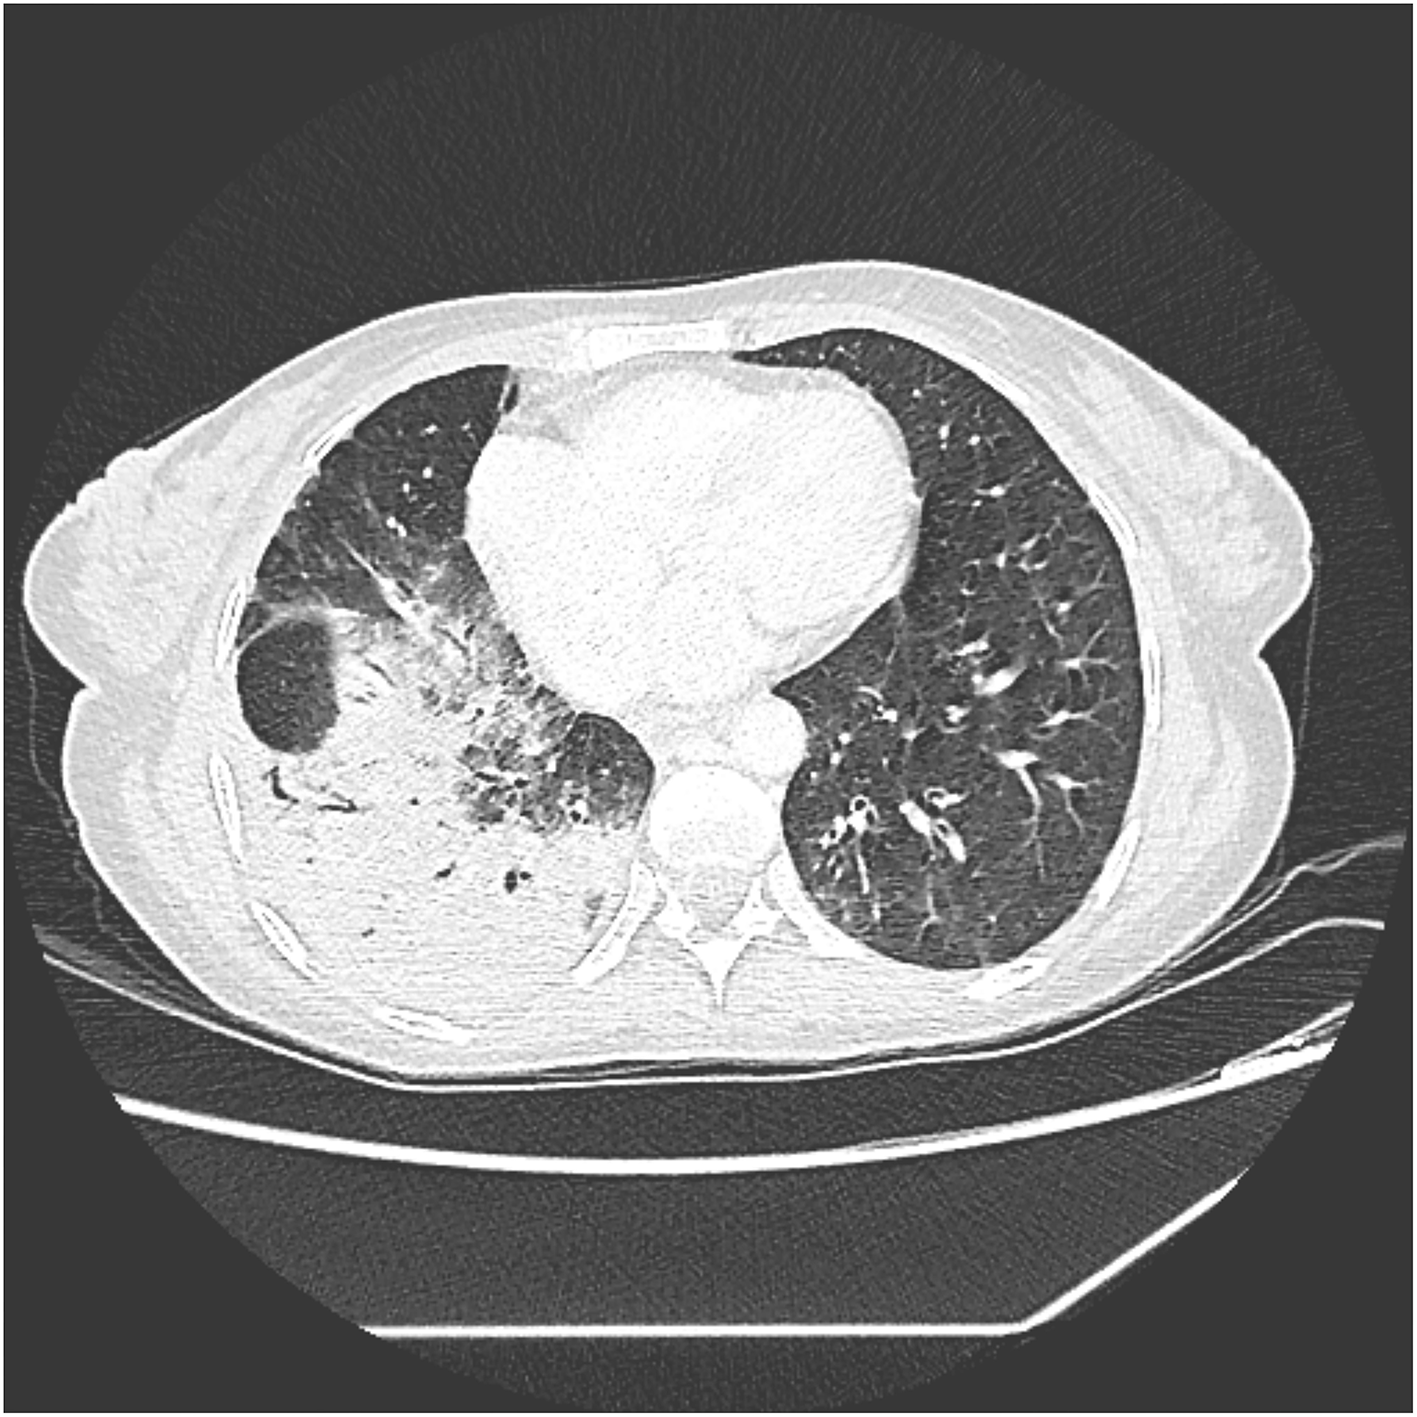

She was re-evaluated 1 month later by the surgical team who decided to continue with the external biliary bypass regarding the liver cirrhosis. We performed a new chest CT scan 4 months after surgery, which demonstrated partial resolution of the inflammatory process. However, it presented a sequelae bronchiectasis with parenchymal fibrosis (Figure 4). At this time, the patient did not present respiratory symptoms or expectoration.

FIGURE 4

Figure 4. Slice of CT scan showing parenchymal fibrosis and bronchiectasis in the right lower lobe.